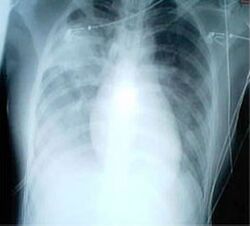

A chest X-ray showing increased opacity in both lungs, indicative of pneumonia, in a patient with SARS

For a case to be considered probable, a chest X-ray must be indicative for atypical pneumonia or acute respiratory distress syndrome.[citation needed]

The WHO has added the category of "laboratory confirmed SARS" which means patients who would otherwise be considered "probable" and have tested positive for SARS based on one of the approved tests (ELISA, immunofluorescence or PCR) but whose chest X-ray findings do not show SARS-CoV infection (e.g. ground glass opacities, patchy consolidations unilateral).[11][12]

The appearance of SARS-CoV in chest X-rays is not always uniform but generally appears as an abnormality with patchy infiltrates.[13]